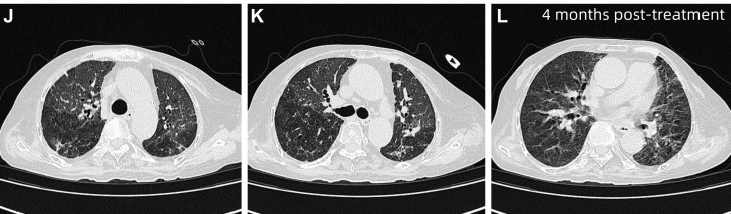

经过超过1个月的治疗后,患者呼吸困难较前改善,但未完全缓解。复查HRCT显示双肺弥漫性斑片状磨玻璃影伴小叶间隔增厚,呈“铺路石样”改变,并见局部空气支气管征。鉴于治疗改善不足,患者在行鼻导管吸氧(3L/min)的同时进一步行

图3 患者治疗1个多月后HRCT,显示双肺弥漫性斑片状磨玻璃影伴小叶间隔增厚,呈铺路石样改变(黄色箭头)